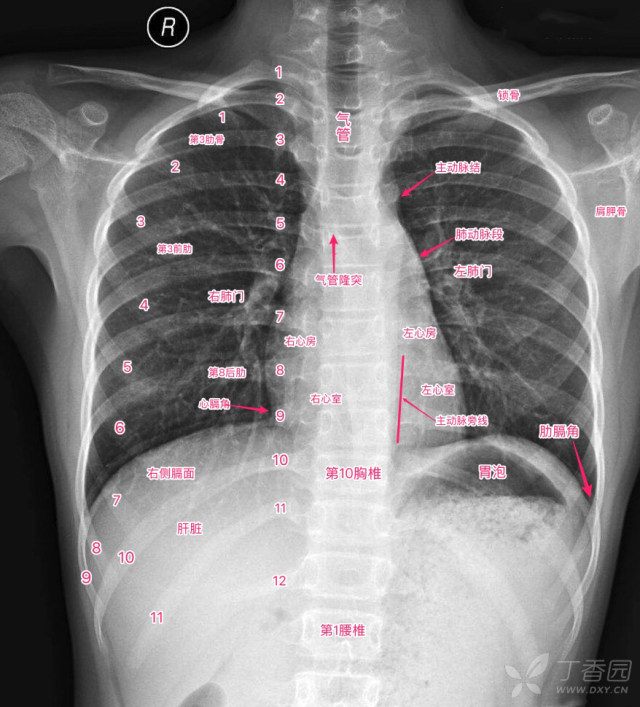

秒懂胸片!